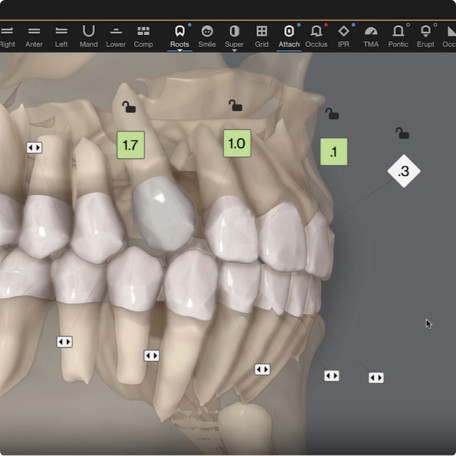

Auto-generates a 3D model with roots, crown, and bone for more-informed treatment planning.

See patients' roots, crowns, and bone in one auto-generated 3D model with new CBCT integration.

Maximizes the efficiency of powerful ClinCheck tools like 3D Controls.

Shows you real root renderings and bone visualizations based on actual scan data.

Simulates root movement along with tooth movement.

Start your treatment planning process in ClinCheck Pro leveraging the now enabled “Roots” button in the tool bar.

Start your treatment planning process in ClinCheck Pro leveraging the now enabled “Roots” button in the tool bar.

Three new views in one integrated platform to enhance treatment planning.

Roots only

Roots with semitransparent bone

Roots and bone

Roots only

Roots with semitransparent bone

Roots and bone